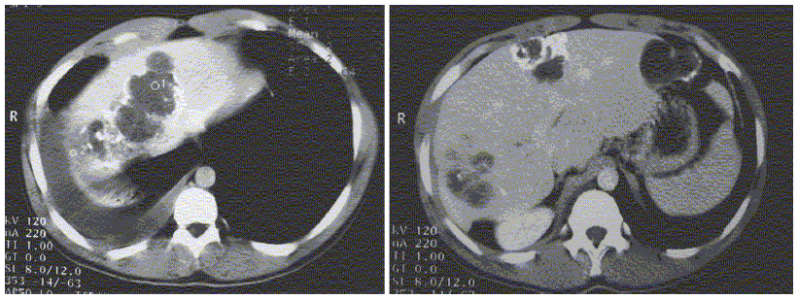

Ejemplo: Un hombre de 56 años de edad es enviado a hospitalización de medicina interna por el diagnóstico de cirrosis hepática de etiología desconocida y síndrome hepatorrenal. El médico residente revisa al paciente y no encuentra evidencia de falla hepática crónica, si bien tiene ascitis. Al evaluar los estudios de laboratorio encuentra que el paciente tiene proteinuria importante, de unos 5 gramos en 24 horas. Por lo anterior difiere con el diagnóstico de envío e inicial el estudio del enfermo como un síndrome nefrótico. Al día siguiente presenta el caso a médico encargado quien revisa al enfermo y encuentra que ha perdido mucho peso, no está edematizado y la presión arterial es normal. El enfermo se queja de síntomas compatibles con neuropatía periférica. La proteinuria del enfermo es a expensas de otras proteínas diferentes a la albúmina y no tiene dislipidemia, de hecho tiene colesterol total de 120 mg/dl (niveles muy bajos).

Con los datos anteriores se hacen dos ajustes del diagnóstico que tienden hacia el diagnóstico definitivo: el paciente no tiene cirrosis hepática y síndrome hepatorrenal (diagnóstico de envío) pero tampoco tiene síndrome nefrótico (diagnóstico de la médico residente). La presencia de pérdida de peso, ataque al estado general, proteinuria, neuropatía periférica, un bloqueo de rama derecha del haz de His en el electrocardiograma y alteraciones de la función hepática orientan del todo al diagnóstico de amiloidosis sistémica. Con ese diagnóstico de trabajo se solicita una biopsia renal y se confirma el diagnóstico de amiloidosis sistémica. Se hizo un “anclaje diagnóstico” hacia la posibilidad más certera.